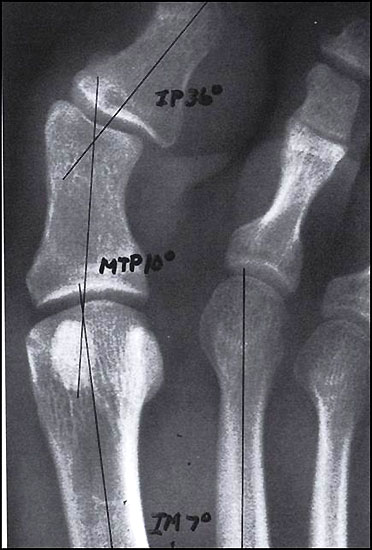

Wenn durch das Anspannen der Muskulatur der 1. Strahl zu einem starren Hebel wird und aussteift, empfehlen wir auf die Durchführung einer TMT-I-Arthrodese zu verzichten und z.B. eine proximale Korrekturosteotomie durchzuführen. So ist nach unserer Auffassung bei jeglicher Dorsalbewegung des 1. Strahles (Instabilität) trotz Anspannung der Peronealmuskulatur (wie beschrieben) die Indikation zur Lapidusarthrodese unabhängig vom Intermetatarsalwinkel gegeben. Bei der Beurteilung des a.p.-Röntgenbildes unter Belastungsbedingungen dient die Bestimmung des Hallux valgus interphalangeus-Winkes und des distalen Artikulationswinkels ggf. zur Indizierung einer additiven Akin-Osteotomie (Abb. 4). Die Stellung des proximalen Artikulationswinkels legt im Falle einer bereits praeoperativ bestehenden Vergrößerung nach Korrektur des Intermetatarsalwinkels eine Korrektur durch eine Reverdin-Green-Laird-Osteotomie nahe (Abb. 5). Die Größe des Intermetatarsalwinkels I/II beeinflusst je nach Größe bei stabilem 1. Strahl die Wahl des jeweiligen Operationsverfahrens.